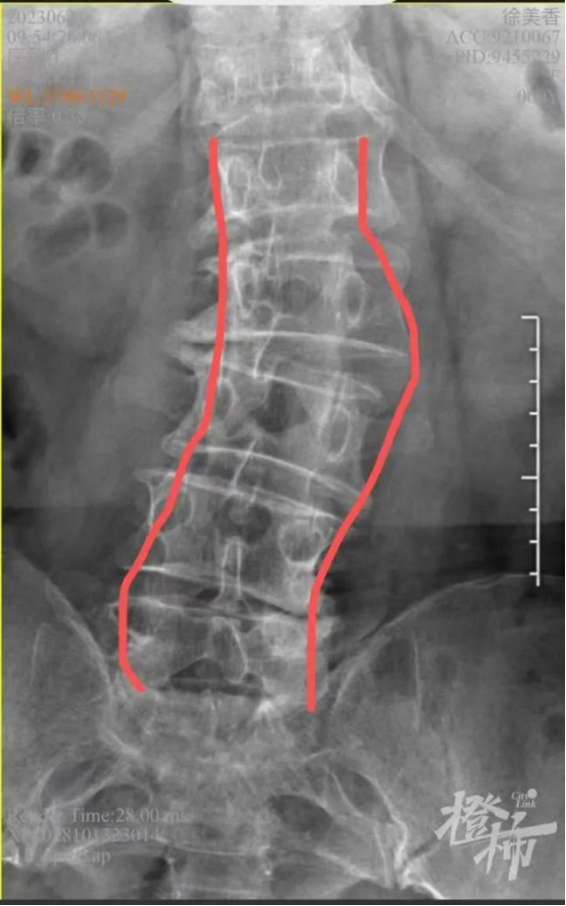

门诊初见李阿姨,她是被推着轮椅进来的。当时她疼痛难忍,病情基本由老伴代述。胡子昂副主任医师从X光片看到,李阿姨的腰椎侧弯cobb角已超过30°,再通过查体问诊中的蛛丝马迹追寻到,李阿姨患的是严重的退行性脊柱侧弯,同时又伴有骨质疏松、椎管狭窄和椎间盘突出,需要手术来缓解症状。

“事实上,从20岁开始,人体的椎间盘就会随着年龄的增长逐步退变。由于椎间盘、腰椎关节等脊柱结构退变老化及骨质疏松等因素影响,到了60岁左右,大概有15%的人会出现脊柱退行性变,男女发病比例约为1:2。”胡子昂说,退变性脊柱侧弯以腰段最为多见,常伴随有腰椎前凸减少、椎管狭窄等病变,导致顽固的腰背痛和下肢神经根症状,严重影响老年人的生活质量。“从外观上,腰椎退行侧弯患者向一侧偏斜、后背不正、弯腰时一侧背部凸起等。从后面看,正常的脊柱像一棵笔直的松树,而退变性侧弯的脊柱像一棵弯曲的柳树。”胡子昂打了个形象的比喻,“如果腰椎侧弯程度不是很严重,也没有明显不舒服,可以先观察,不予治疗,定期拍片复查。对于侧弯程度比较严重,且合并有腰椎管狭窄引起的相应症状,比如腰酸、腰痛、腰部严重无力,甚至压迫双下肢神经,出现腿麻、腿疼、腿无力,间歇性跛行等症状,还是建议手术治疗。”